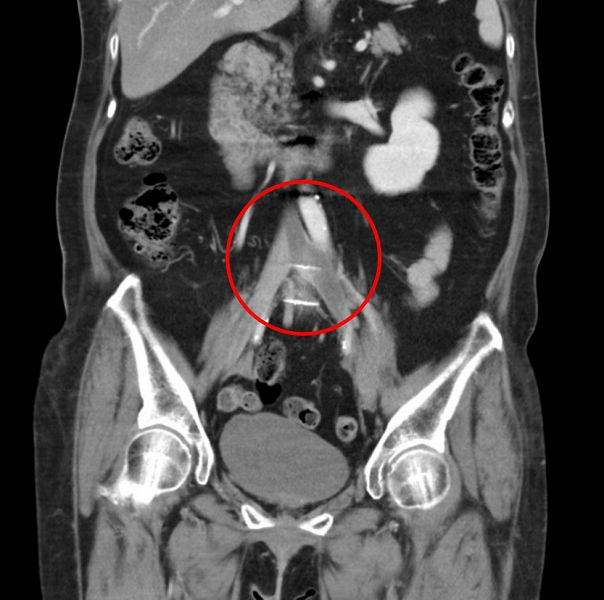

透過超音波及電腦斷層檢查,郭女士罹患的左側下肢深部靜脈血栓,位於左下髂肢靜脈和下腔靜脈的交叉處,屬於高位血栓,因下腔靜脈是腹部以下血流匯集的血管,包括骨盆、子宮、卵巢、泌尿道的靜脈都會經過,下半身血流的主要幹道被大塊血栓塞住,血液回流差,才會導致骨盆腔以下部位疼痛異常。王惠生醫師與郭女士討論治療方案,隔日就進行機械抽栓手術。

清除血栓後,王醫師用血管內超音波檢查,發現有一段明顯狹窄的區域,推測可能是因長期勞動導致椎間盤突出,往前推的脊椎骨壓迫靜脈往腹部大動脈造成「髂靜脈壓迫症候群」;為了維持日後管徑的暢通,在此處靜脈置放支架。